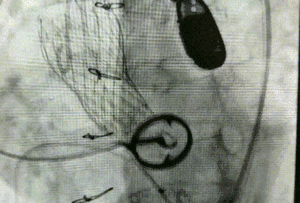

经充分准备后,王焱带领心内科,心外科,超声,麻醉多学科团队,将预先安装的瓣膜装置仔细调整位置,在透视影像、超声的共同指导下平稳释放,瓣膜成功置入。随即进行冠脉造影及心脏超声复查,观察到植入的瓣膜位置非常精确,手术取得了圆满成功。

术后即刻示意图像:瓣膜释放位置良好